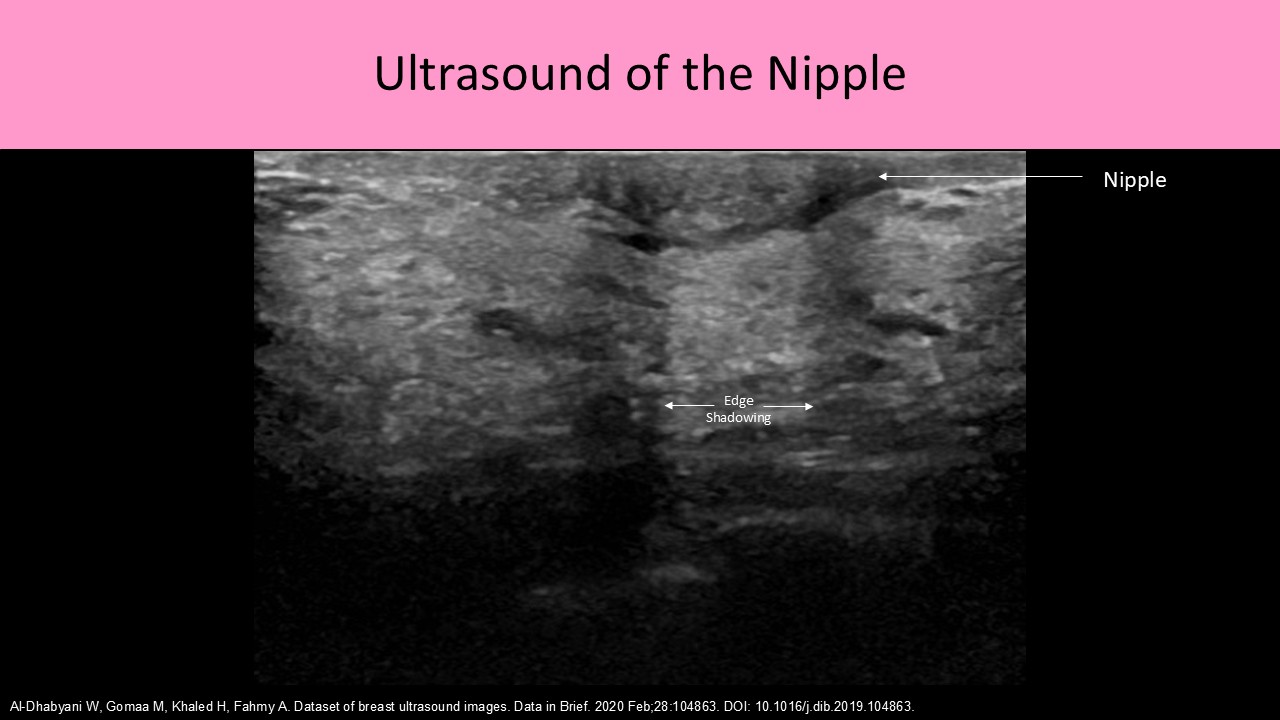

- Lactiferous Sinus or Ampulla which is an area of ductal enlargement just prior to the opening to the nipple; usually 2-3mm in diameter indicates a normal finding

- Collection ducts or Excretory ducts - 15-20 openings that excrete the milk from the nipple

- Nipple